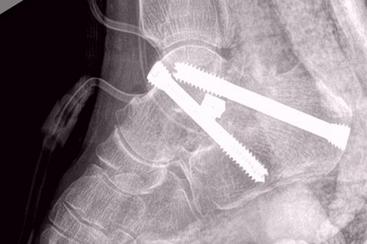

在現代社會(hui) ,骨損傷(shang) 和關(guan) 節病越來越常見。人體(ti) 的關(guan) 鍵位置,如踝部和四肢關(guan) 節的骨缺損,將會(hui) 令患者產(chan) 生疼痛和行走姿勢不當等問題。